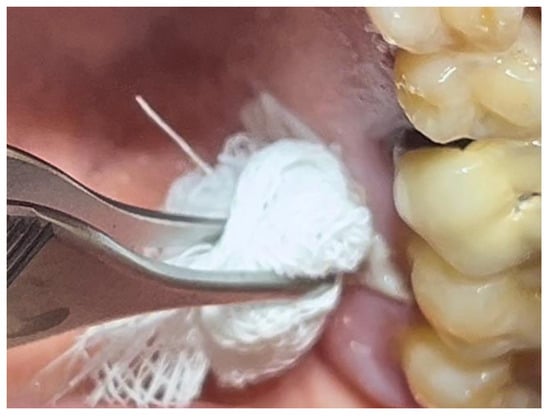

A similar technique was used in a 45-year-old patient with controlled hypertension, treated for the extraction of tooth 1.6 (Figure 11) and subsequent post-extraction implant-prosthetic rehabilitation (Figure 12). The surgical site was treated with bone graft material (Bio-Oss®—Geistlich), and a small amount of Glubran II was applied (Figure 13). Once again, Glubran II proved to be highly effective in stabilizing the graft material at the surgical site, providing excellent hemostasis and strong mechanical resistance from the film formed after polymerization (Figure 14).

Figure 13. Stabilization of synthetic bone material at the surgical site, undergoing implant-prosthetic rehabilitation with Glubran II using an endodontic needle.